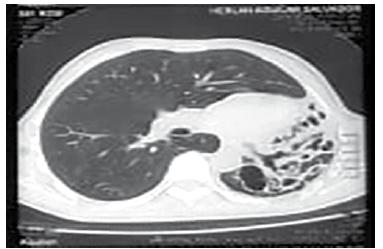

El cuadro N° 4, ilustra la extensión y localización de las BQs, la ubicación de las mismas por segmentos pulmonares muestra que 8 pacientes tienen las lesiones a nivel de un lóbulo pulmonar llámese lóbulo superior e inferior derecho o izquierdo, en 9 casos las lesiones se ubican en dos lóbulos generalmente lóbulos superiores y 6 pacientes calificados como difusos con daño pulmonar importante en toda su estructura, el patrón tomográfico más frecuente fue la variante cilindrica (Figura N°1) en 21 pacientes y la variante sacular o quística (Figura N° 2) en 2 pacientes.

Figura N° 1. Bronquiectasias Cilindricas

BRONQUIECTASIAS CILINDRICAS EN LA BASAL DEL LÓBULO INFERIOR IZQUIERDO PIRÁMIDE

La TTAR permite valorar la extensión, localización y morfología de las BQs, la tabla 4 muestra que estas fueron bilobares en 9 pacientes (39,1%), 8 de ellos tienen los lóbulos superiores afectados y 6 la forma multilobar o difusa, diferentes estudios muestran una mayor prevalencia de la forma cilindrica o tubular33 sobre la forma quística o varicosa, en nuestro estudio destaca nítidamente la forma cilindrica con un 91,3%.